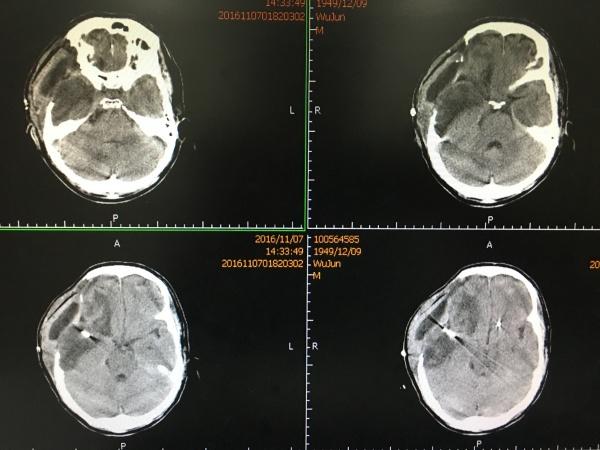

再过一周,再次复查CT示:

硬膜下积液较前稍增加,中线基本回位,积液未造成明显占位效应,故我们决定继续观察,必要时可以予以Ommayya囊植入、积液引流术。

患者现病情平稳,我们很有信心现状可进一步改善。